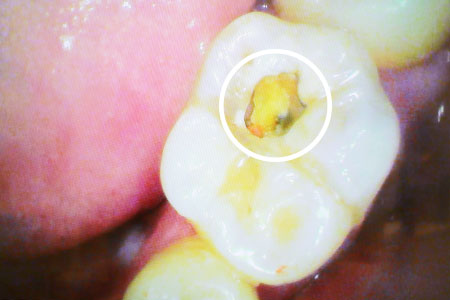

虫歯治療例 少し虫歯をとると大きな虫歯を発見

虫歯治療例 大きな虫歯